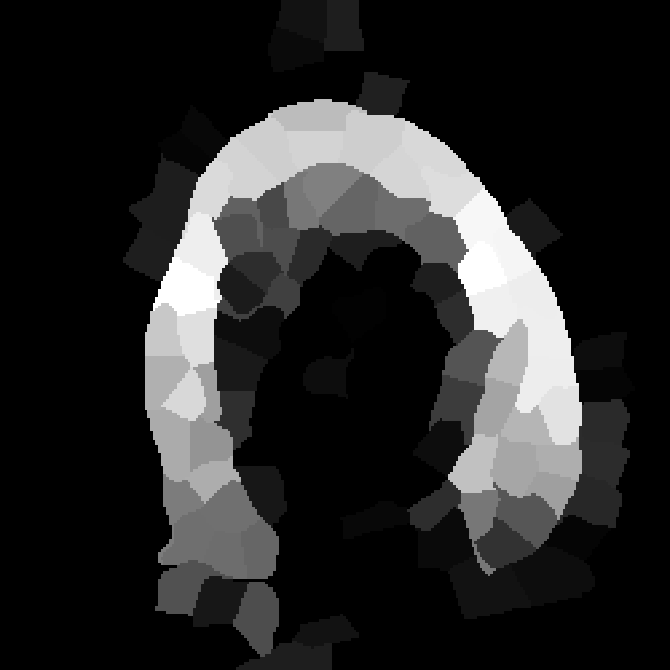

To emphasize the interest of our method, we propose a framework to perform fast segmentation and labeling from an image database. SuperPatchMatch is well adapted to deal with huge and constantly growing databases since no learning phase is required, contrary to most existing approaches based on supervised machine learning [17, 18], or recent neural network methods [19, 20]. We apply SuperPatchMatch to the challenging Labeled Faces in the Wild (LFW) database [21], where the goal is to extract hair, face, and background within images decomposed into superpixels, and to the segmentation of tumors on non-registered Magnetic Resonance Images (MRI). Finally, SuperPatchMatch outperforms, in terms of computational cost and accuracy, state-of-the-art methods.

To demonstrate the interest of the superpatch structure and the SPM algorithm, we adapt our approach to exemplar-based labeling. We consider two experiments: face labeling on the LFW dataset [21], and segmentation and labeling on non-registered medical images from the BRATS dataset [49].

V-C Non-Registered MRI Segmentation Experiments

To demonstrate the robustness of the superpatch structure and the proposed framework, we apply SPM to brain tumor segmentation on multi-modal non-registered Magnetic Resonance Images (MRI). Classical patch-based and multi-atlas structure segmentation methods are based on registered subjects. Consequently, they cannot be efficiently applied in this non-registered context, due to the substantial variation in tumor shape and locations. Superpixels enable to better capture the tumor geometry, thus increasing the segmentation accuracy. Superpixel and supervoxel-based approaches have been applied to tumor segmentation [54]. However, in this work, the neighborhood is not considered and the ANN search is exhaustive, and computed on a large multi-modal histogram descriptor, leading to prohibitive computational time.

SPM can be efficiently applied to tumor segmentation since it quickly finds good correspondences without image registration, and uses the superpixel neighborhood to improve the matching. In this application, the segmentation is computed from a superpixel decomposition [1], then each region (tumor or background) is labeled with SPM.

We present results obtained on the MICCAI multi-modal Brain Tumor Segmentation (BRATS) dataset [49]. This challenging dataset contains real and simulated patient data, with overall poor resolution and large variation of tumor shape and position. For both types, high grade (HG) and low grade (LG) tumors are provided with four modalities: T1, contrast enhanced T1 (T1C), T2, and FLAIR. Overall, there are 20 and 10 real patient data with respectively HG and LG tumors, and 25 images for both HG and LG simulated tumor data. We use the same SPM parameters as in Section V-B, taking a multi-modal histogram, containing the levels of gray intensity on all MRI modalities as descriptor for superpatch matching, and performing the regularization (8) at the pixel scale to compare with pixel-wise ground truths. Each subject is segmented by the remaining of its type in a leave-one-out procedure.

In Fig. 12, we show several tumor segmentation results for all data types.

In Table II, we compare results obtained using different descriptor structures:

patch-based [48], superpixel-based [54],

and superpatch-based (= pixels).

We use the Dice coefficient [55] as evaluation metric,

measuring the overlap between the automatically segmented structure and the ground truth.

The superpixel-based approach

appears very limited since it fails at capturing the tumor context and their location in other images.

Regular patches are also limited in this context, due to the variations in the structure shapes.

Superpatches provide a robust descriptor, since they follow image intensities and capture the superpixel neighborhood,

leading to more accurate segmentation.

These experiments demonstrate that superpatches within the SPM framework provide fast and accurate segmentation results

even on non-registered multi-modal images with poor resolution.